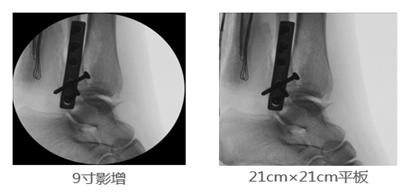

2、成像视野:在图像尺寸方面, 9英寸平板与9英寸影增相比,平板探测器成像为“方形”,较同尺寸的影像增强器的“圆形”成像而言,有效视野面积扩大了22%,使医生的观察视野更加开阔,极大的提高了手术的效率,同时提高了各种手术的安全性。